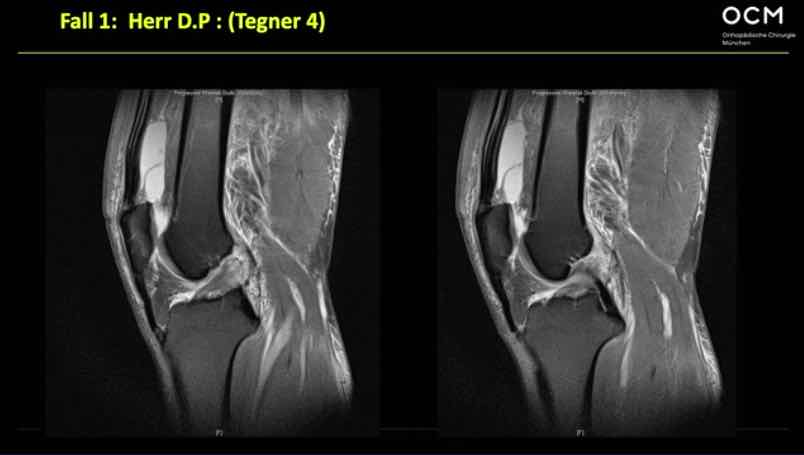

Management VKB-Revision: Diagnostik & Präoperative Planung A. Achtnich

Operative Strategie: Periphere Instabilität - wann und wie? M. Herbort

Simple Case T. Diermeier

Complex Case C. Kittl

Complication Case S. Scheffler